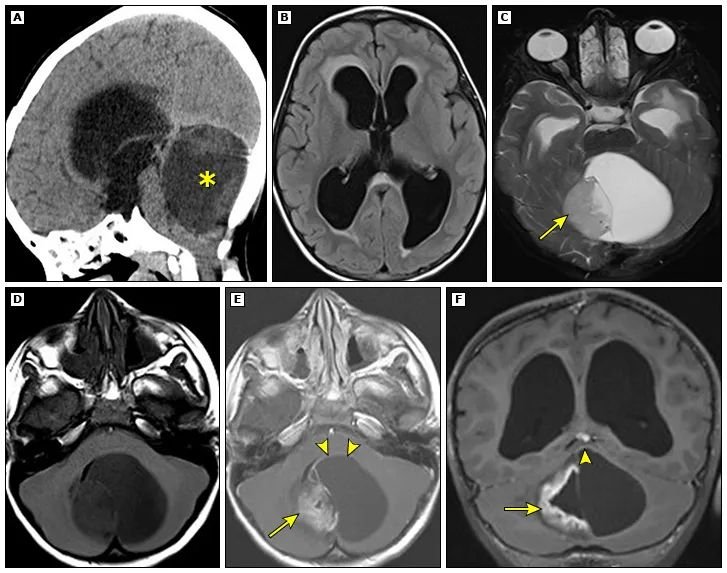

在MRI上,毛细胞型星形细胞瘤的T2加权像通常表现为高信号,T1信号多变。在颅后窝和大脑半球,大多数毛细胞型星形细胞瘤表现为界限清楚、扩张的肿块,包括强化的壁结节,周围有囊肿(图1)。脑干或视路肿瘤可能为实性或囊性,有不一的增强模式。周围无水肿或有轻微水肿。对于儿童颅后窝肿瘤,与肿瘤实性部分相关的T2高信号程度有助于区分毛细胞型星形细胞瘤与髓母细胞瘤。

图1:一名5岁儿童患有毛细胞星形细胞瘤,因梗阻性脑积水就诊。矢状位平扫CT(A)显示大的低密度小脑肿块(*),该肿块压迫脑干并导致三脑室和侧脑室扩大。横轴FLAIR(B)MRI显示经室管膜水肿,提示急性脑积水。横轴T2-(C)、T1-(D)以及横轴(E)和冠状(F)平面中的对比后T1加权图像显示带有壁结节的囊性小脑肿块(箭头)。壁结节内以及囊肿壁的一部分(箭头)内存在增强。